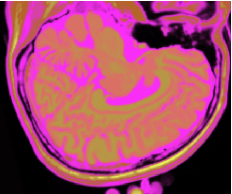

As figuras 2 (banda 0), 3 (banda 1) e 4 (banda 2) mostram a fatia 97 de um volume de imagens sagitais com 181 fatias e 0% de ruído, ponderadas em PD (densidade de próton), T1subscript𝑇1T_{1} e T2subscript𝑇2T_{2}, enquanto a figura 5 ilustra a composição colorida R0-G1-B2 da mesma fatia. Pode-se notar no topo do crânio, na parte inferior das imagens, a presença de artefatos, que podem ser resultantes de erros no simulador, mas que não são prejudiciais à análise, uma vez que, neste trabalho, não é dada ênfase à análise anatômica.

Figura 3: Imagem de RM da fatia 97 ponderada em T1subscript𝑇1T_{1}

Refer to caption